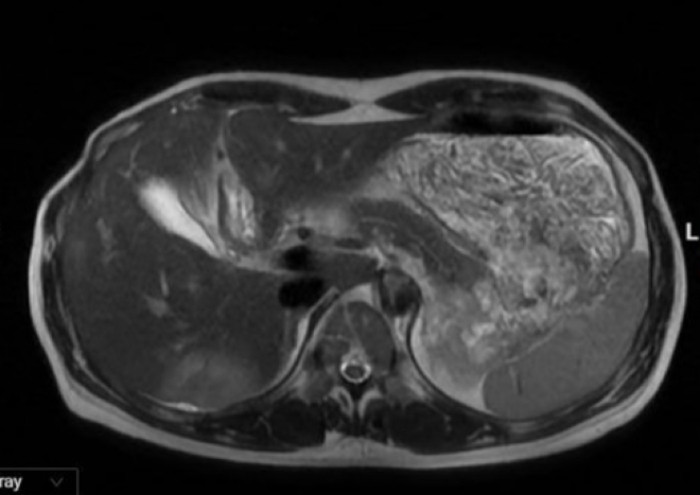

Kết quả siêu âm và chụp cộng hưởng từ (MRI) cho thấy, gan phải có hai tổn thương, kích thước lần lượt khoảng 4,5 cm và 1 cm, nghi do ký sinh trùng gây ra.

2 tổn thương trên gan phải được trên hình ảnh chụp MRI ổ bụng. (Ảnh: BVCC)